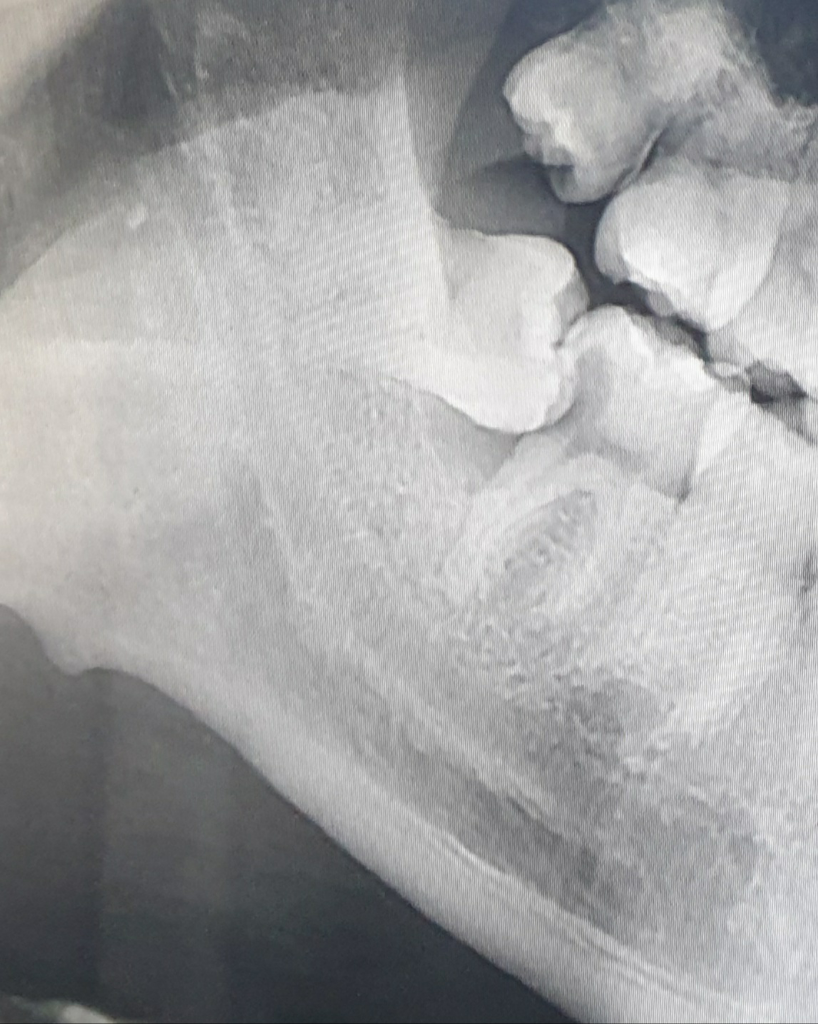

어금니 한쪽 뼈가 없는 경우 사랑니가 나오면서 어금니 지탱할 뼈를 만들 수 있나요???

제 어금니 옆이 뼈가 없어서 사랑니를 뽑게 되면 어금니 옆에 뼈가 자라지 못하고 살이 찰 경우 그 사이에 음식물이 끼게 되고

사랑니가 정말정말 조금씩 나오면서 그 위아래로 뼈가 조금씩 따라나오면서 자라게 되고 그로 인해 나중에 어금니를 지탱할 뼈가 생길거라고 하더군요

하지만 제가 보기에는 사랑니를 빼는게 맞는 것 같아요. 일단 사랑니는 안그래도 깊숙이 있어 신경치료를 하기가 힘든데 저 기울어진 각도로 신경치료를 한다는게 가능이나 한지부터가 의문이고,

앞 어금니와 사랑니가 닿아서 충치가 생긴건데 이 상태에서 어떻게 사랑니가 더 나온다는건지도 모르겠고,

사랑니를 빼서 뼈가 안차서 음식물이 끼이는 것보다 저 상태로 놔둬서 사랑니와 어금니 사이에 음식물이 끼이는게 더 많고 꼈을 때 빼기도 힘들 것 같아요. 사랑니를 빼서 음식물이 끼일까봐 걱정이라면 그 치과에서 질문자님께 이러이러한 문제가 있을 수 있으니 신경써서 깨끗하게 관리하라고 일러주면 될 일이라는 생각이 들어요.

저정도 사랑니라면 저같으면 발치를 하는게 좋을것같다는 생각을 합니다. 발치를 해도 뼈가 찰만큼 찰것같습니다.

해당 어금니는 교정적으로 끌어올리거나 방향을 주어 당기지 않으면 맹출하기가 쉽지 않습니다. 즉 누워서 사랑니가 나고 있으므로 현재 사랑니는 발치를 해야 합니다. 물론 말씀하신 것처럼 치조골이 차오르는 효과를 기대할 수 있으나 오히려 음식물이 더 많이 끼어 잇몸 질환으로 이어질 가능성이 큽니다. 해당 사랑니는 발치해야 하는 상태이며 보존적으로 사용할 수 없습니다.